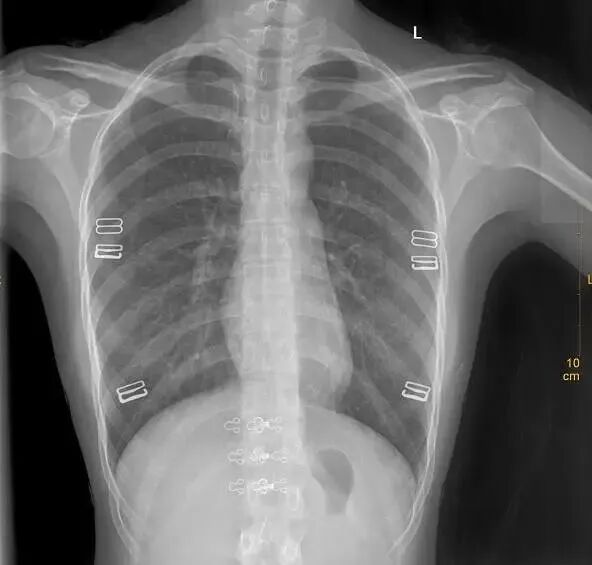

②这个好像简单一点。

X光拍片为什么要等【影像科普】拍片为什么会要求脱衣服?_https://www.jmylbn.com_新闻资讯_第5张